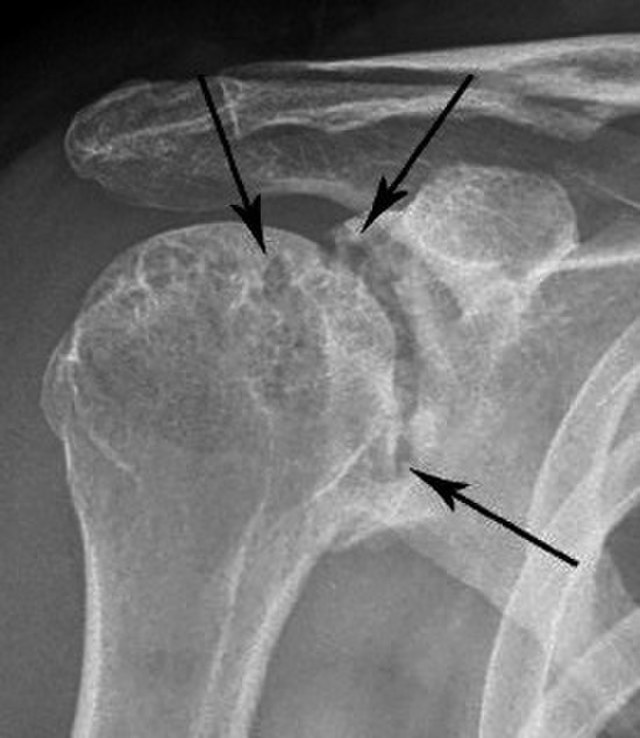

- Chest X-ray – can be used to image any problems or abnormality in lung pathology (e.g. pleural effusions etc).